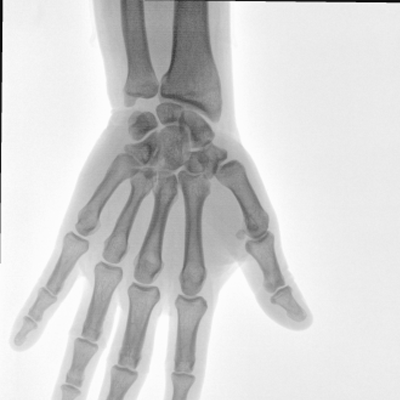

大尺寸動態平板探測器,高DQE、低噪聲、圖像清晰。采用多分辨率圖像增強處理技術,不同部位不同圖像處理算法,滿足客戶多樣化的需求。

采用智能變頻脈沖透視技術,優化圖像質量的同時降低輻射劑量,呵護醫患健康